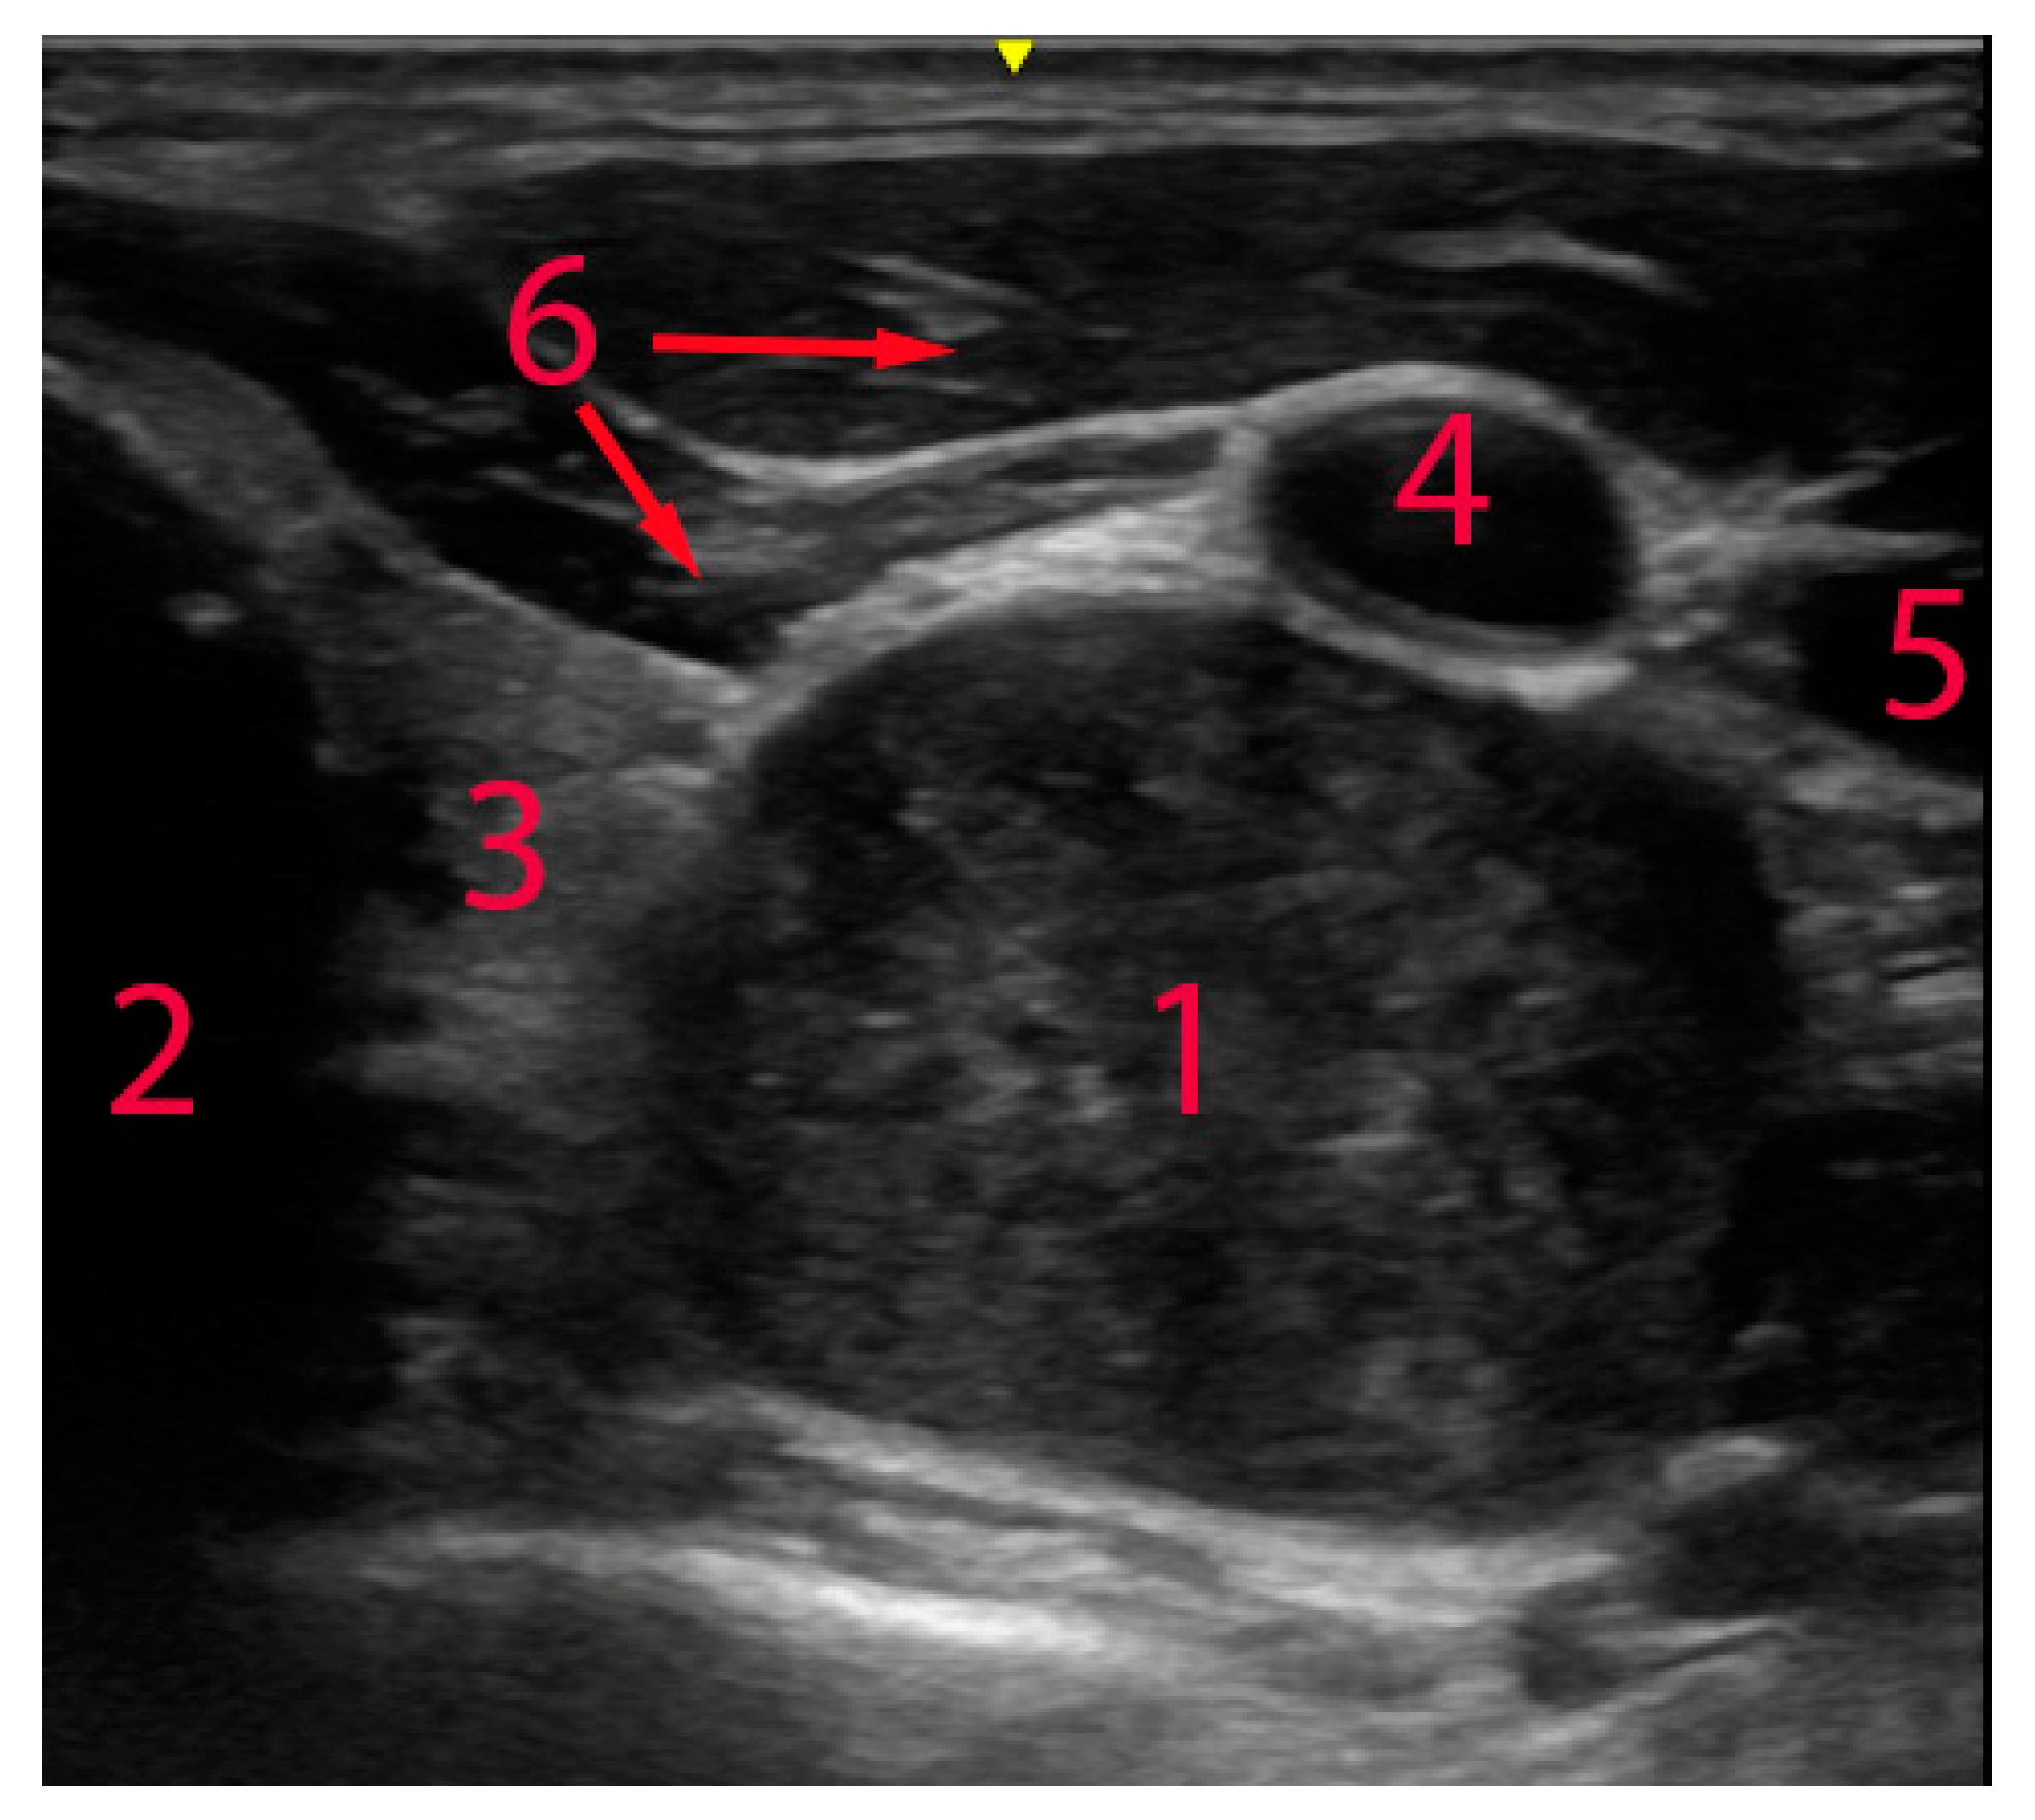

| USG | Schwannoma | Hypoechoic mass, regular margins, contextual anechoic areola, multiseptate hypoechoic lesion, macro- and microcalcifications. Contrast-enhanced ultrasonography may be another possibility to distinguish schwannomas; however, data are limited to several case reports. The tumour usually appears as strong, inhomogeneous enhancement both in early and in late phases. Elastography usually indicates dense stiff tissue. | [3,9,10,12,13,25,27,29,31] |